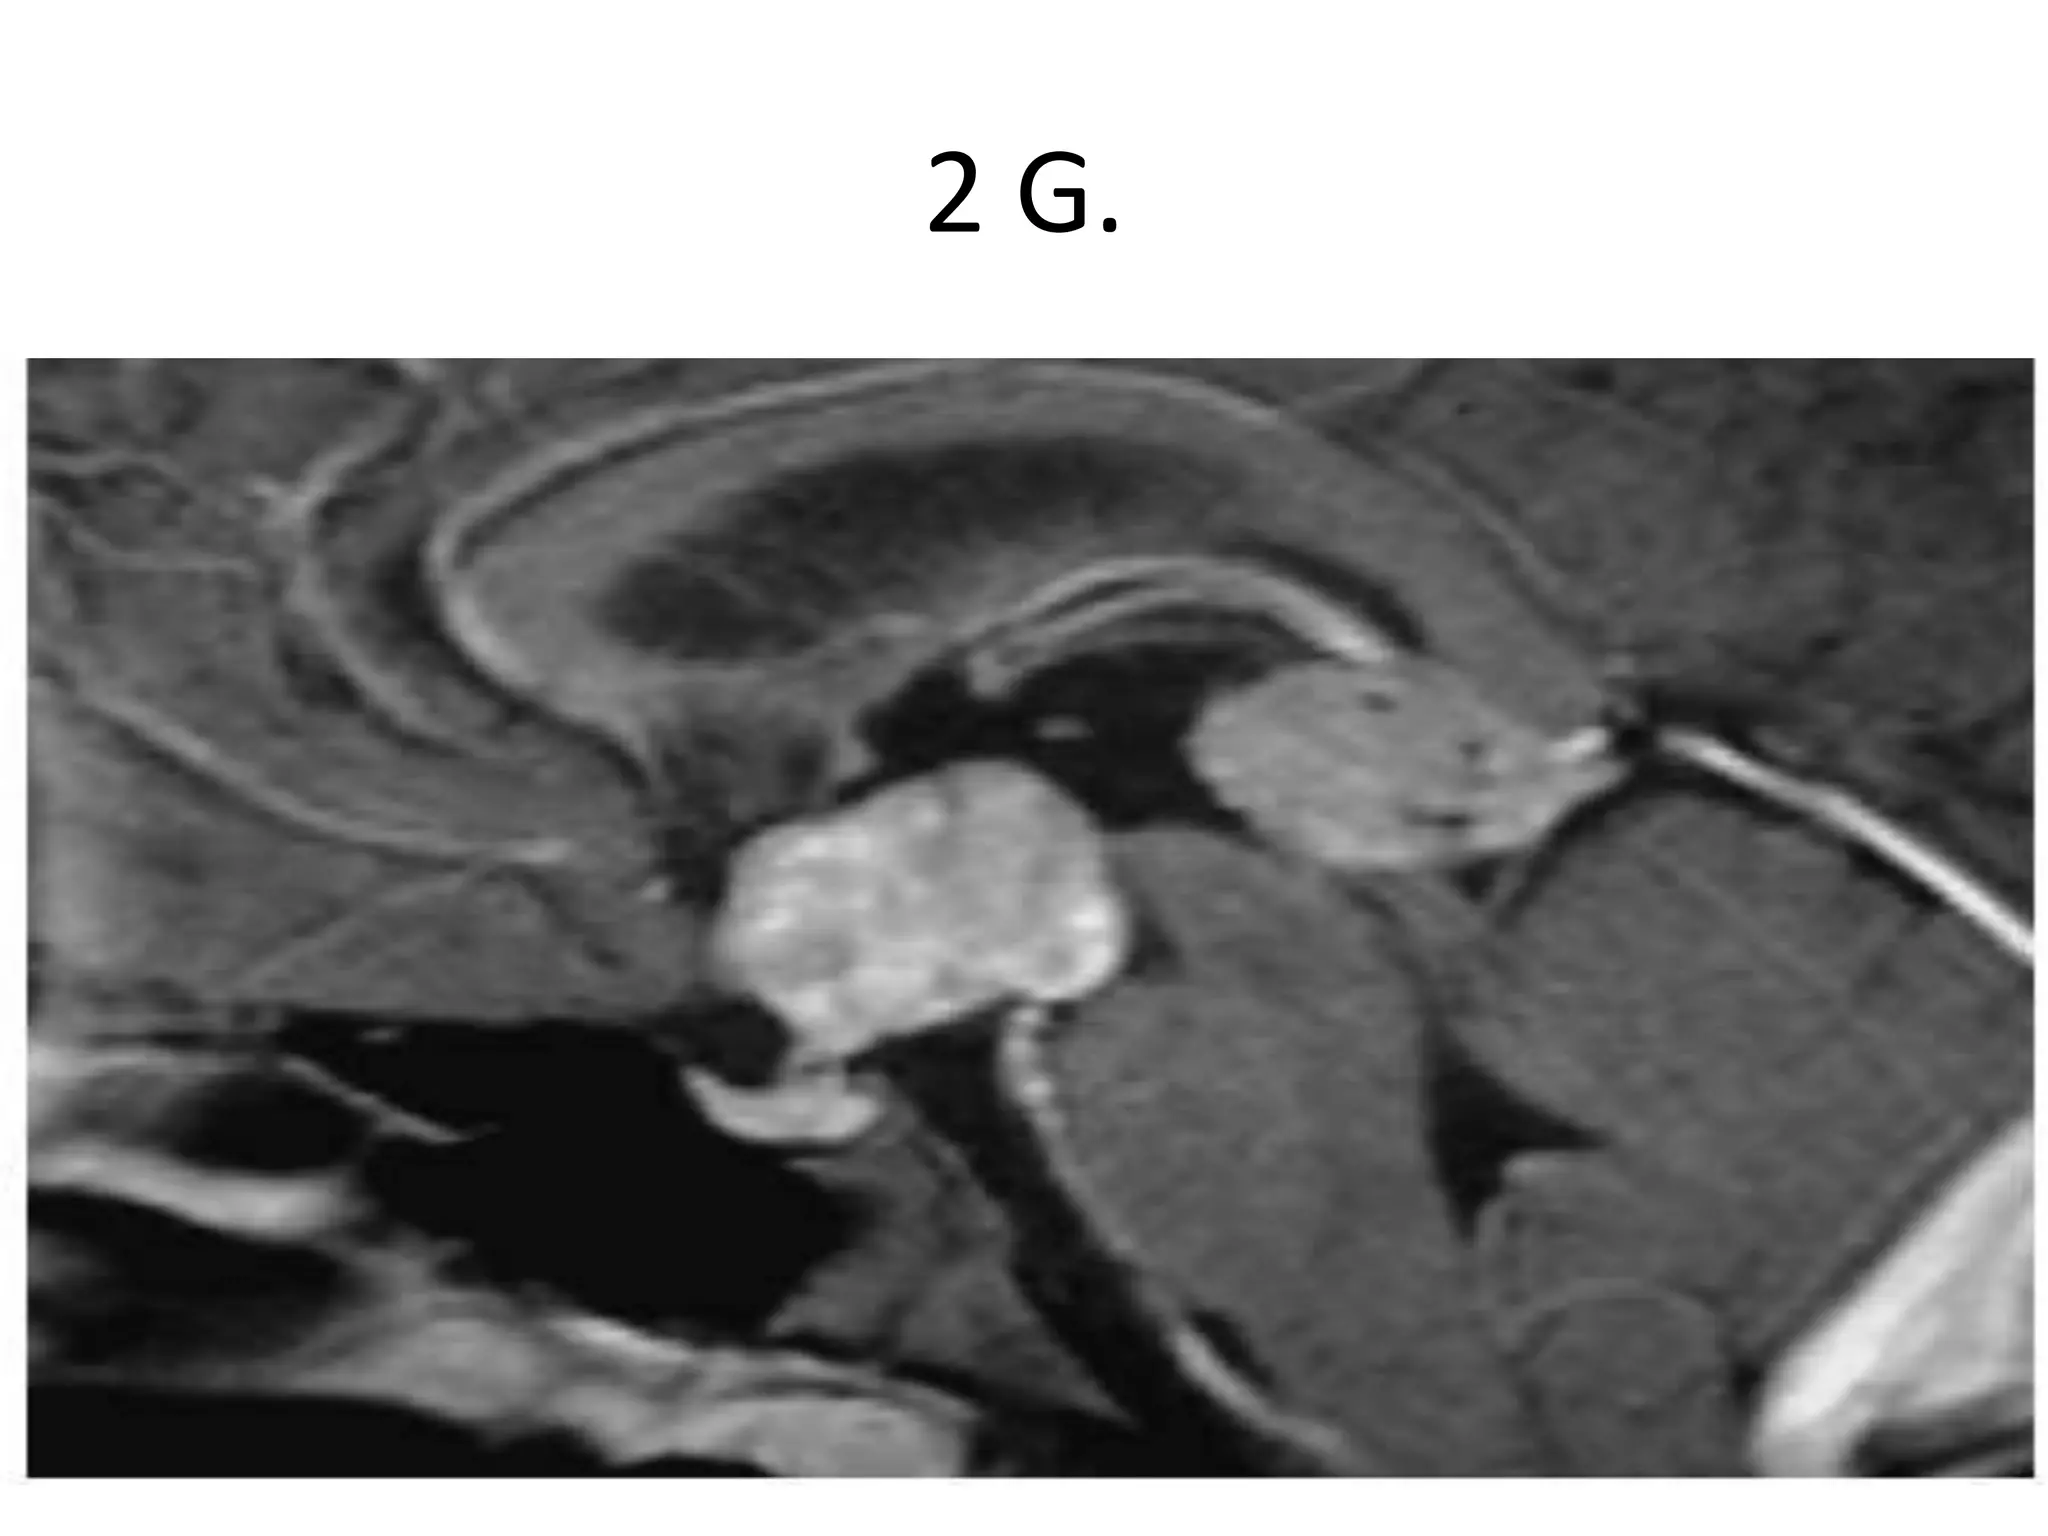

2 G.

A rare case of posterior fossa CP, and account for 1-4%, CT and MR images show PFCP,